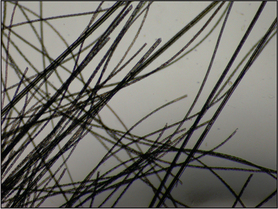

Hair plucks

Microscopic examination of hair plucks may be useful to detect Demodex spp. mites (Fig. 2.2) and Cheyletiella spp. or louse eggs. Hair plucks are very useful when taking samples from areas that are difficult to scrape, such as the feet in the case of pododemodicosis, when skin scraping would require sedation. Fifty to 100 hairs are plucked and mounted in liquid paraffin on a glass slide under a coverslip. The hair tips, shafts and bulbs should all be carefully examined. One study showed deep skin scraping to be more sensitive than hair plucks in cases of localized and squamous demodicosis, and therefore demodicosis should not be ruled out on the basis of not finding mites on hair plucks.

Figure 2.2 Hair pluck from a case of pododemodicosis with adult mites and egg (arrowed).